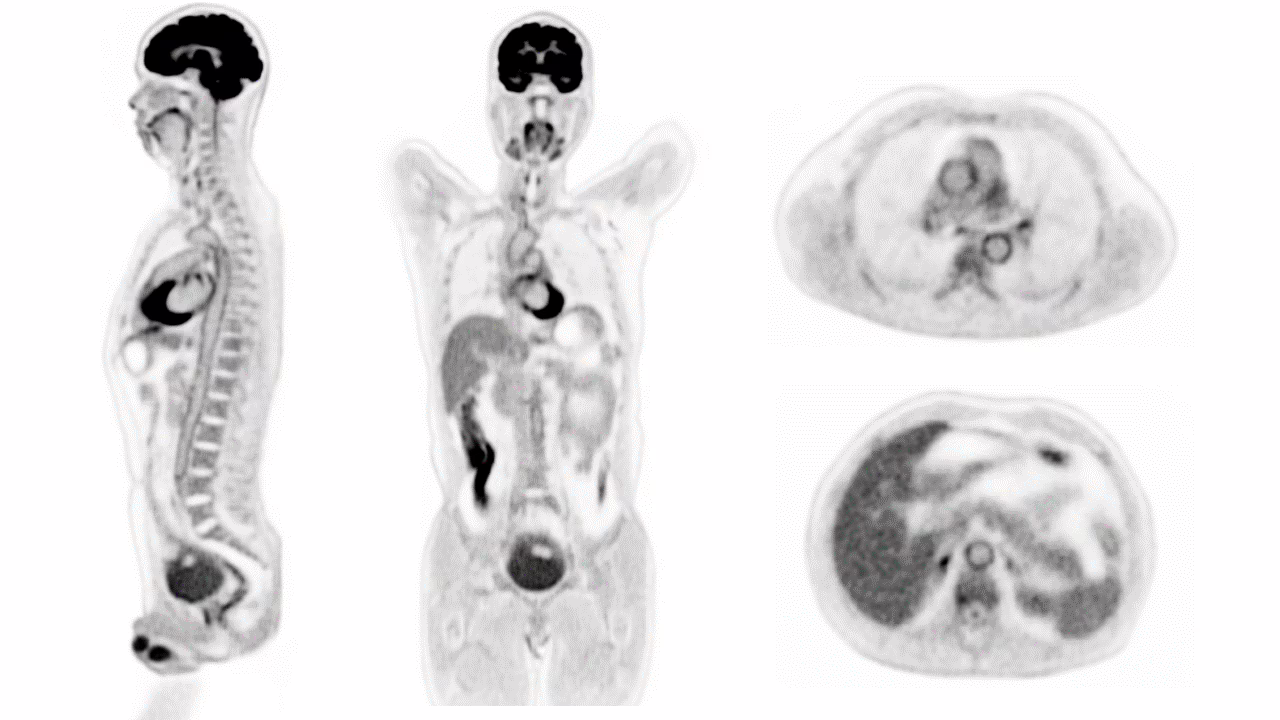

Grandi novità in ambito di imaging medicale. Grazie ad un nuovo scanner, frutto dell’ ingegno di Davis Simon Cherry e Ramsey Badawi della UC Davis, è ora possibile acquisire un’ immagine 3D total body con un’unica scansione. Questo gioiello tecnologico si chiama EXPLORER e combina due tecnologie: quella della PET (Tomografia ad Emissione di Positroni) e quella della TC (Tomografia Computerizzata). Oltre a produrre scansioni con un livello di dettaglio sorprendente, EXPLORER impiega solamente 20-30 secondi per ottenere la scansione. Ma i vantaggi non sono finiti: l’immagine può essere ottenuta con una dose di radiazioni 40 volte inferiore a quella utilizzata dalla tradizionale PET.

Explorer. Credits immagine: UC Davis

La PET è una tecnica diagnostica di medicina nucleare che permette di ottenere immagini mediche grazie a traccianti radioattivi somministrati per via endovenosa. Questo esame permette di studiare in modo non invasivo la fisiologia, il metabolismo e i percorsi molecolari nell’essere umano. Esistono migliaia di scanner PET, ma EXPLORER è l’unico dispositivo al mondo in grado di valutare ciò che sta accadendo in tutti gli organi e tessuti del corpo simultaneamente.

Dotato di oltre 500mila rilevatori, lo scanner è in grado di produrre immagini di qualità senza precedenti con una velocità fino a 40 volte superiore a quella della dei dispositivi attualmente in commercio.

Il livello di dettaglio è sorprendente, soprattutto una volta ottimizzato il metodo di ricostruzione.

Commenta Badawi, direttore di medicina nucleare presso la UC Davis Health e vicepresidente per la ricerca presso il Dipartimento di Radiologia.